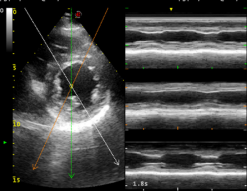

这套超声系统拥有完整的心脏功能检测方案。搭 载更加宽频的相控阵探头,拥有更加完善的小动物心 脏超声解决方案。可以进行心脏解剖 M 型(CMM) , M 型取样线可 360 度任意旋转,并可同时设定 3 条自 由角度取样线。同时显示同一时相 3 条线上组织 M 型 信息,实现在同一个心动周期中,在同一时相对不同 的心肌节段、瓣膜进行对比观察和测量分析。

心脏解剖 M 型(CMM):

M 型取样线可 360 度任意旋转,并可同时设定 3 条自由角度取样线。同时显示 同一时相 3 条线上组织 M 型信息,实现在同一个心动周期中,在同一时相对不同的 心肌节段、瓣膜进行对比观察和测量分析。可应用于心脏和腹部探头(心脏功能评估)。

大鼠心脏

小鼠心脏